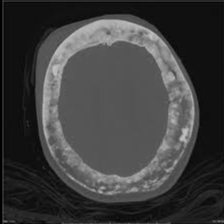

_ Skull involvement that presents as:

Headaches

Increased hat size

Hearing loss if it involves the bone surrounding the inner ear and/or narrows the auditory foramen

Loss of vision and other cranial nerve lesions may also occur (however it is uncommon)

_..X-ray imaging reveals thickened bone cortex with shaggy radiolucent lytic lesions interspersed throughout the bone matrix. Bone with these features are described as having a cotton wool appearance.